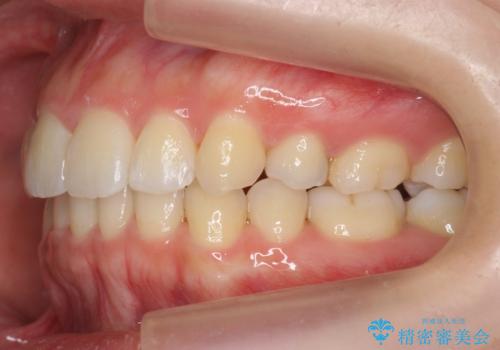

再矯正 昔ワイヤーで治療 前歯の並びを再度きれいに

- 小さいころに小臼歯を抜歯しワイヤー矯正をしたが、すき間が空いてきて、前歯の並びが戻ってしまったとのこと。

インビザラインライトという部分矯正コースで、全体矯正に比べ、比較的安価に治療しました。

前歯の並びが格段にきれいになり、大変喜んでいただけました。